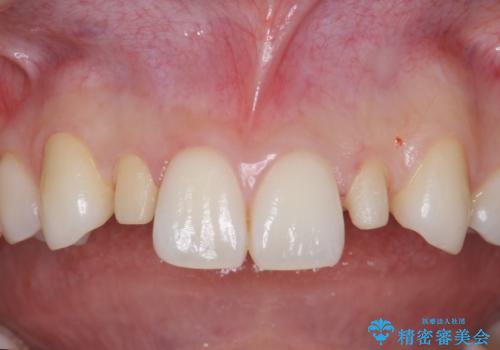

- 前歯のがたつきと小さな歯の形を治したいと来院。

前から2番目の歯が小さく、細くとがった形になっていました。

大きくしようにも、幅が少ない上に、また、内側に入ってしまっているため、矯正治療で前歯を並べてからセラミックでかぶせることにしました。